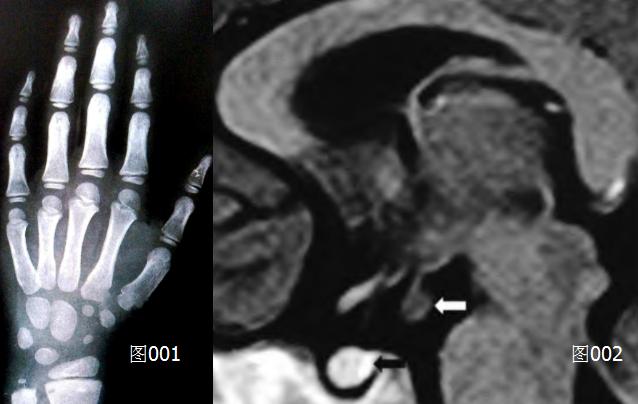

(3)骨龄:约6岁(正常骨龄与生活年龄差别<1年内,见图001)。

(4)下丘脑垂体MRI:垂体饱满,呈类圆形,上缘弧形隆起,垂体高度11 mm,强化好,鞍上池灰结节区可见一个7mmx8mm占位(白色箭头处所指),形态规则,带细蒂,呈等T1等T2信号.T1加权相无强化(见图002)。